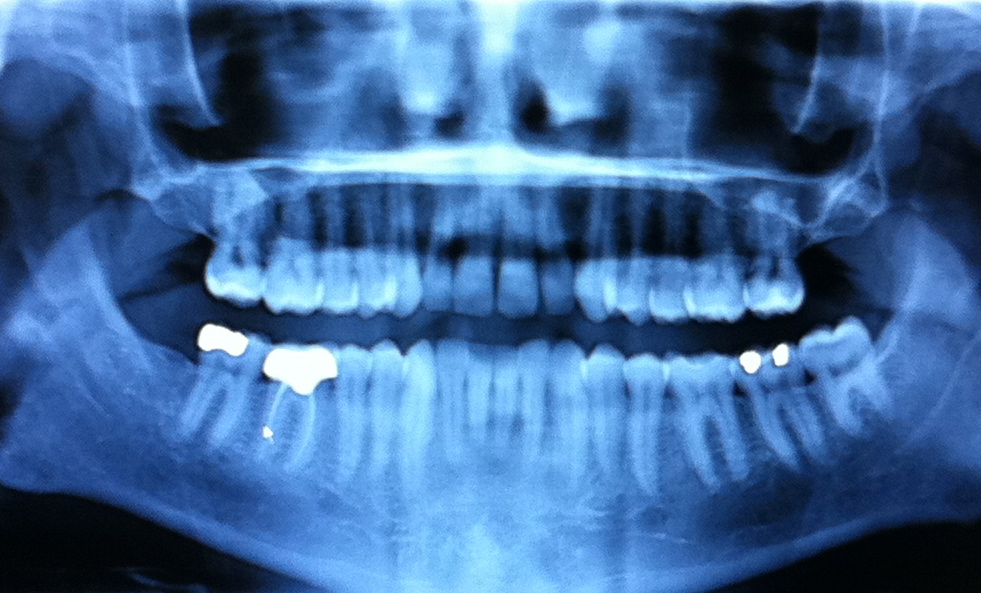

*jasonarnold74: Photo: teeth http://t.co/U6Eczhbu

teeth